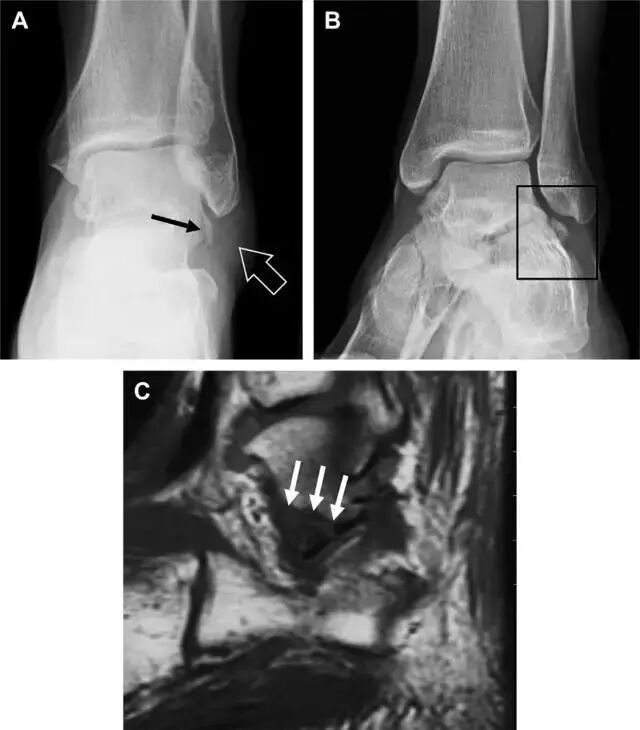

胫骨后踝骨折

涉及到三角韧带和外侧副韧带(LCL)的复杂性骨折常常不难发现,尤其是存在表面软组织肿胀时。然而,后胫腓韧带牵拉引起的胫骨后踝骨折则很难发现。这些骨折大小不一(图 2),却很重要,因为他们常与胫骨远端螺旋骨折有关,或者是三踝骨折的一部分。

图 2 胫骨后踝骨折。A 侧位片示来源于胫骨后踝的一个小骨折碎片(箭头),因踝部扭伤导致;B 另一位跖屈损伤的患者,侧位片示一个大骨折块(箭头)

胫骨结节骨折

Tillaux 骨折,是足外旋外展时,胫腓前韧带牵拉引起的一种胫骨结节撕脱性骨折。斜位片上可见典型表现(图 3)。

图 3 摔倒后胫骨结节骨折。A 正位片示一细小斜型骨折线(箭头);B 侧位片示正常;C 冠状位 CT 三维成像更清晰地显示了骨折线和骨折块大小(空箭头);D 矢状位 CT 多维重建图像示骨折位置(箭头)